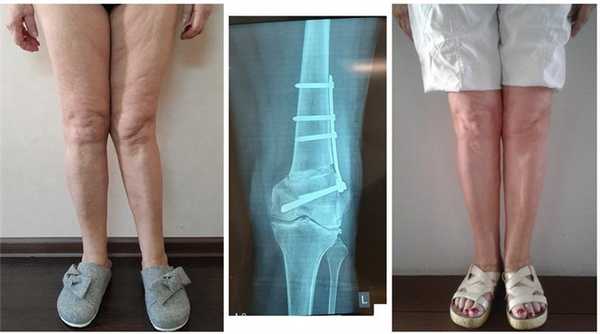

Пациентов фотографировали до, в процессе коррекции и после завершения лечения. При этом соблюдали определенные правила: ровный фон, камера на уровне коленных суставов, фокусное расстояние около 3 метров. Соблюдение этих правил позволяло получать качественные изображения с минимальными искажениями и производить сравнение внешнего вида ног на различных этапах коррекции. Особое внимание уделяли качеству выполнения фотографий до начала лечения у пациентов с идиопатической Х-образной формой ног, поскольку именно они представляли особое значение при обсуждении плана и прогноза коррекции (Рисунок 3).

Документирование, в первую очередь, выполнение фото и видео до операции, значительно облегчают оценку формы нижних конечностей на завершающих этапах коррекции с помощью аппарата Илизарова и позволяют получить желаемый результат, удовлетворяющий пациентов не только по клинико-рентгенологическим показателям, но и по внешнему виду.

Рисунок 3 - Фото до операции в свободной стойке (а, б) и в положении максимального сближения стоп (в, г), а также рентгенограмма нижних конечностей этой пациентки по всей длине в свободной стойке (д).

Часто встречающаяся ситуация - вальгусная деформация ног + наружная ротация + укорочение левого бедра 2 см. Слева деформация более выражена, поскольку деформированы были и бедро, и голень. Провели двухэтапную коррекцию. 1 этап - левое бедро, 2 этап - обе голени. Genu valgum (в отличие от genu varum) часто обусловлена деформацией бедренных костей. Поэтому для определения объема операции обязательно нужен рентген ног по всей длине.

При такой значительной деформации уже к 50 годам развивается деформирующий артроз коленных суставов преимущественно с вовлечением наружных отделов. Когда деформация прогрессирует, операция по исправлению оси становится уже не настолько эффективна. Кроме того, вальгусное колено намного сложнее в плане эндопротезирования.